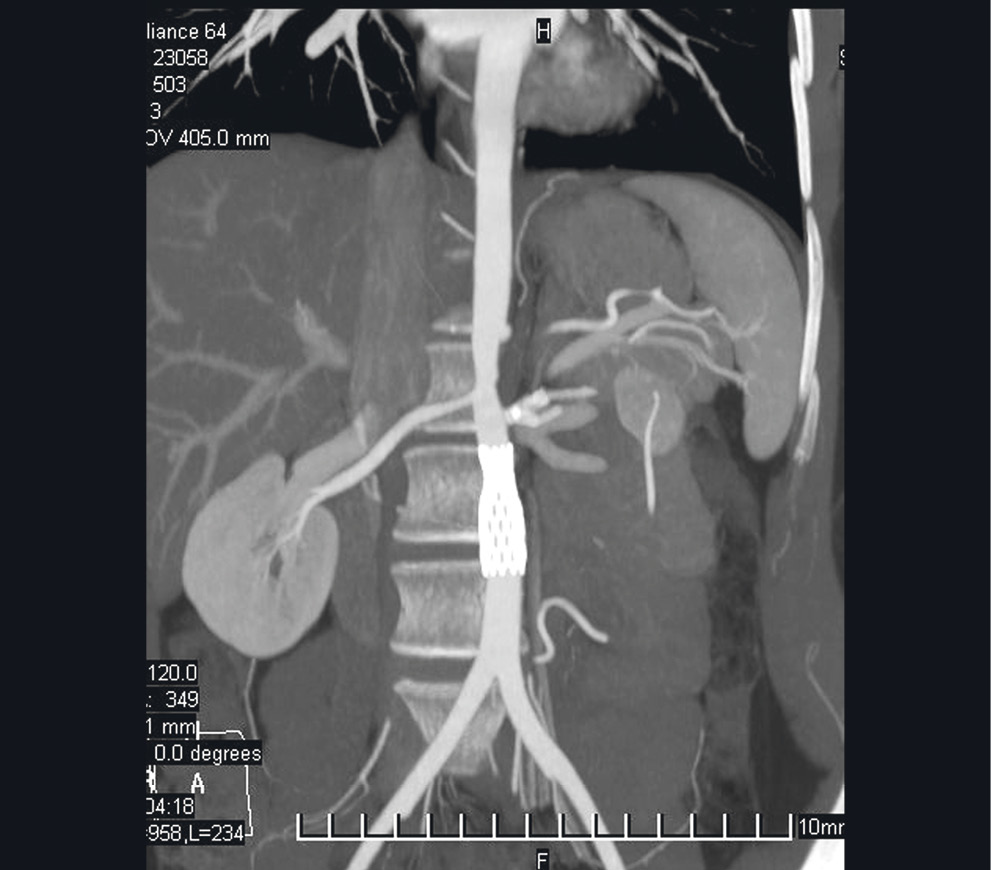

В ноябре 2010 г. в отделении кардиохирургии Донецкого клинического территориального медицинского объединения (ДОКТМО) было проведено оперативное вмешательство в объеме стентирования брюшного отдела аорты, бифуркационного стентирования почечных артерий слева (рис. 2, 3).

Рис. 3. Та же пациентка: визуализация стентов при проведении компьютерной томографии

В послеоперационном периоде наблюдалось стойкое снижение артериального давления до 110/50 мм рт. ст. Пациентка была консультирована ревматологом и переведена в ревматологическое отделение ДОКТМО для дообследования и уточнения диагноза.